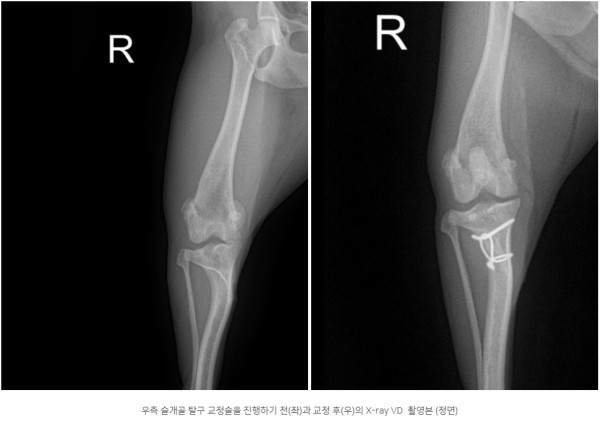

내원 후 보행 상태와 관절 촉진을 확인한 뒤 X-ray 촬영을 진행했습니다.

촬영 결과,

✔️ 양쪽 슬개골 탈구가 진행된 상태였으며

✔️ 기존에 있던 슬개골 불안정성에 낙상 사고가 더해지며 증상이 급격히 악화된 것으로 판단되었습니다.

특히 우측 슬개골 탈구의 진행 정도가 더 심한 상태였고,

현재 보행 장애의 주된 원인으로 판단되었습니다.

슬개골 탈구가 진행된 상태에서 낙상사고로 충격이 더해진 현재의 아이의 상태를 알려드리고

먼저 진행이 조금 더 심한 우측 슬개골 탈구 교정 수술을 결정하게 되었습니다.